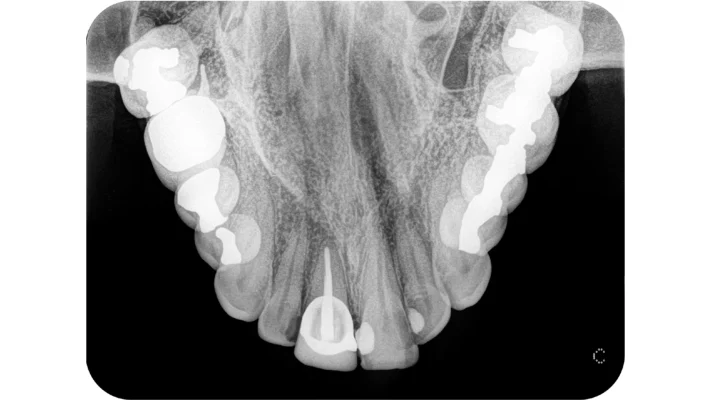

CS 7600 nabízí vše, co očekáváte od vysoce výkonného intraorálního systému záznamu na fólie, tedy rychlost, kompaktnost konstrukce, trvale vysokou kvalitu snímků a kromě toho ještě něco navíc. Naše jedinečná technologie „Exponuj a jdi“ (Scan and Go) automatizuje provoz systému, vylučuje chyby a šetří náklady.

CS 7600 poskytuje rychle a vysoce kvalitní snímky. První snímek uvidíte do pěti vteřin a skenování a zobrazení statusu je hotovo v několika minutách.

• Vynikající rozlišení obrazu, vysoká rychlost

• Zobrazovací software s intuitivní navigací získá ze snímků maximum diagnostické informace